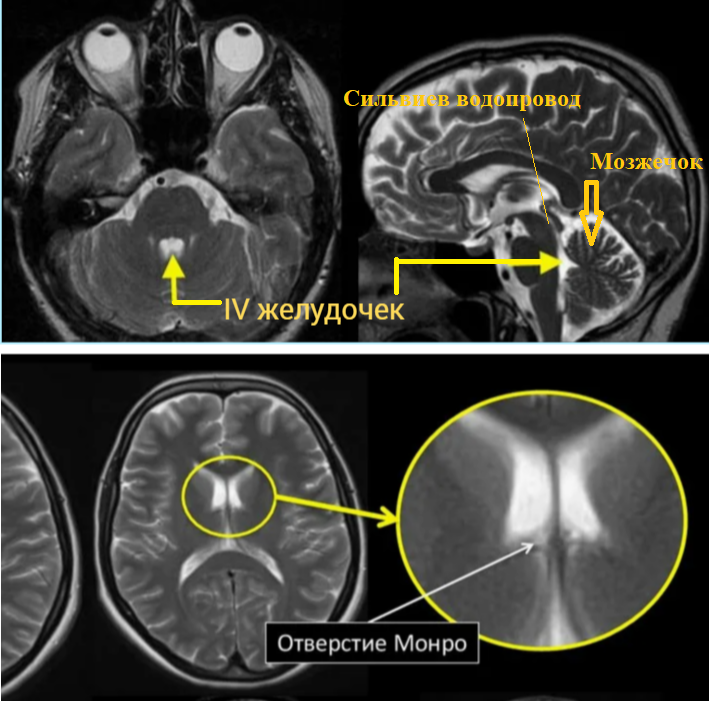

Отверстия Люшка и Мажанди - это отверстия в полости IV желудочка мозга, через которые имеется сообщение ликвора с субарахноидальным пространством. Отверстие Монро соединяет каждый боковой желудочек с III

Краткая схема ликвороциркуляции

В норме из боковых желудочков мозга ликвор через отверстие Монро поступает в III желудочек, оттуда по водопроводу в IV желудочек, через отверстия Мажанди и Люшка - в подпаутинное пространство мозга. Последние в области основания мозга формируют ряд базальных цистерн, из которых ликвор поступает в конвекс, омывая полушария головного мозга.